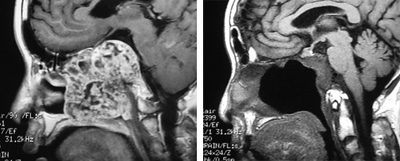

鼻咽纤维血管瘤

骨化纤维瘤

斜坡脊索瘤

图8 鼻内镜外科技术的延伸:鼻颅底、鼻眼相关精准手术